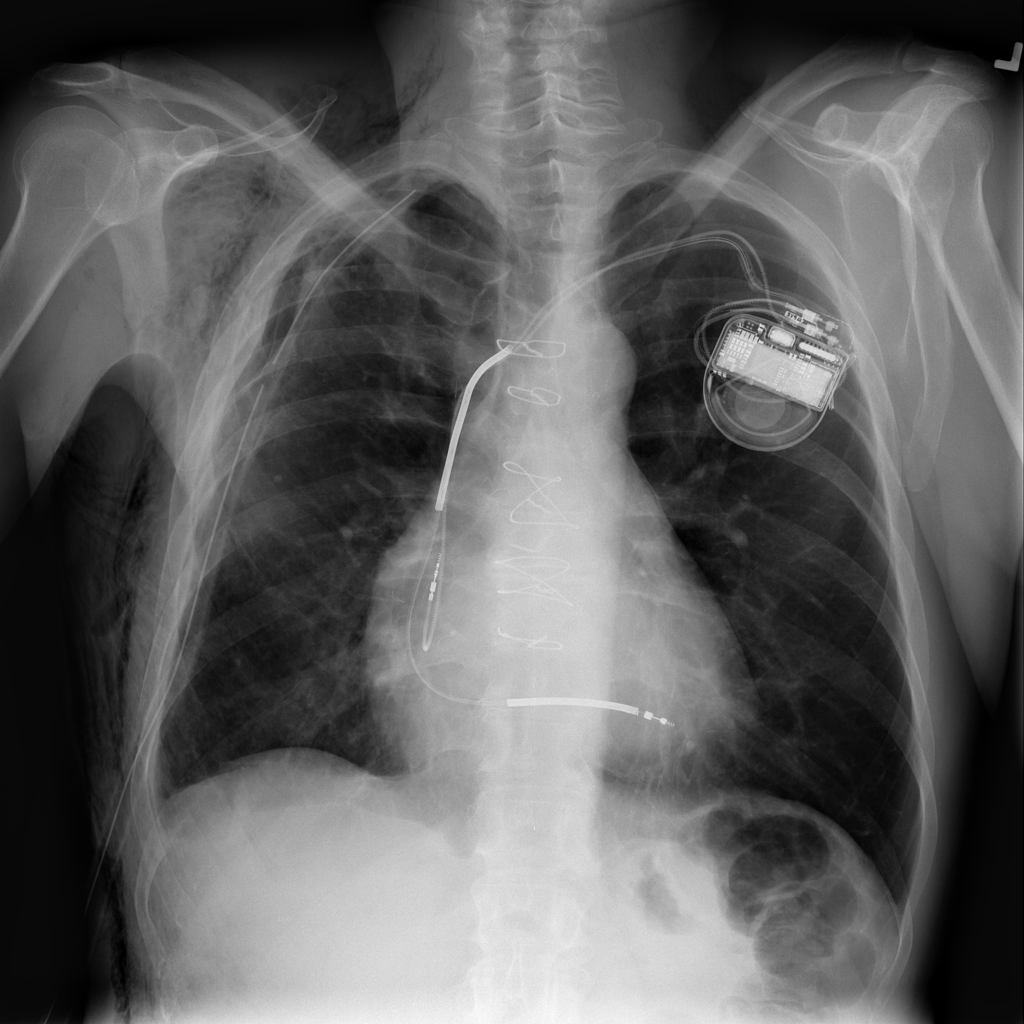

Pneumothorax

Pneumothorax means air is present outside the lung in the pleural space, which can allow part of the lung to collapse. It is an important imaging finding because the size and clinical impact can vary widely.

Support Devices

Support devices on chest X-ray include lines, tubes, and implanted hardware whose position may affect safety and management.

Showing up to 90 reference images for Pneumothorax.